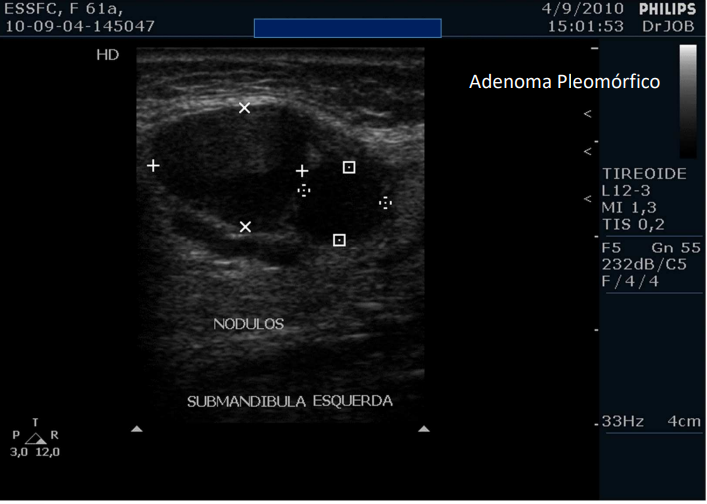

Examine essa imagem e descreva

Vemos dois nódulos em região submandibular esquerda